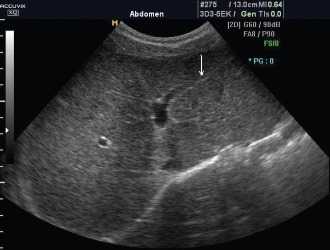

Рис. 1. На эхограмме селезенки больного циррозом печени и портальной гипертензией определяются мелкие диффузные гиперэхогенные включения (точечные кальцификаты).

Рис. 2. Эхограммы больного циррозом печени и портальной гипертензией.

a) Повышение эхогенности и неоднородная структура печеночной паренхимы с наличием узлов.

b) Видна расширенная пупочная вена.

На эхограмме в левой косой проекции (рис. 1) визуализируются диффузные гиперэхогенные включения (точечные кальцификаты) в селезенке, состоящие из телец Гамна-Гэнди. При сканировании в правом подреберье (рис 2b) визиализируется печень повышенной эхогенности, с неоднородной структурой, образованием узлов в ее паранхиме и расширением пупочной вены.